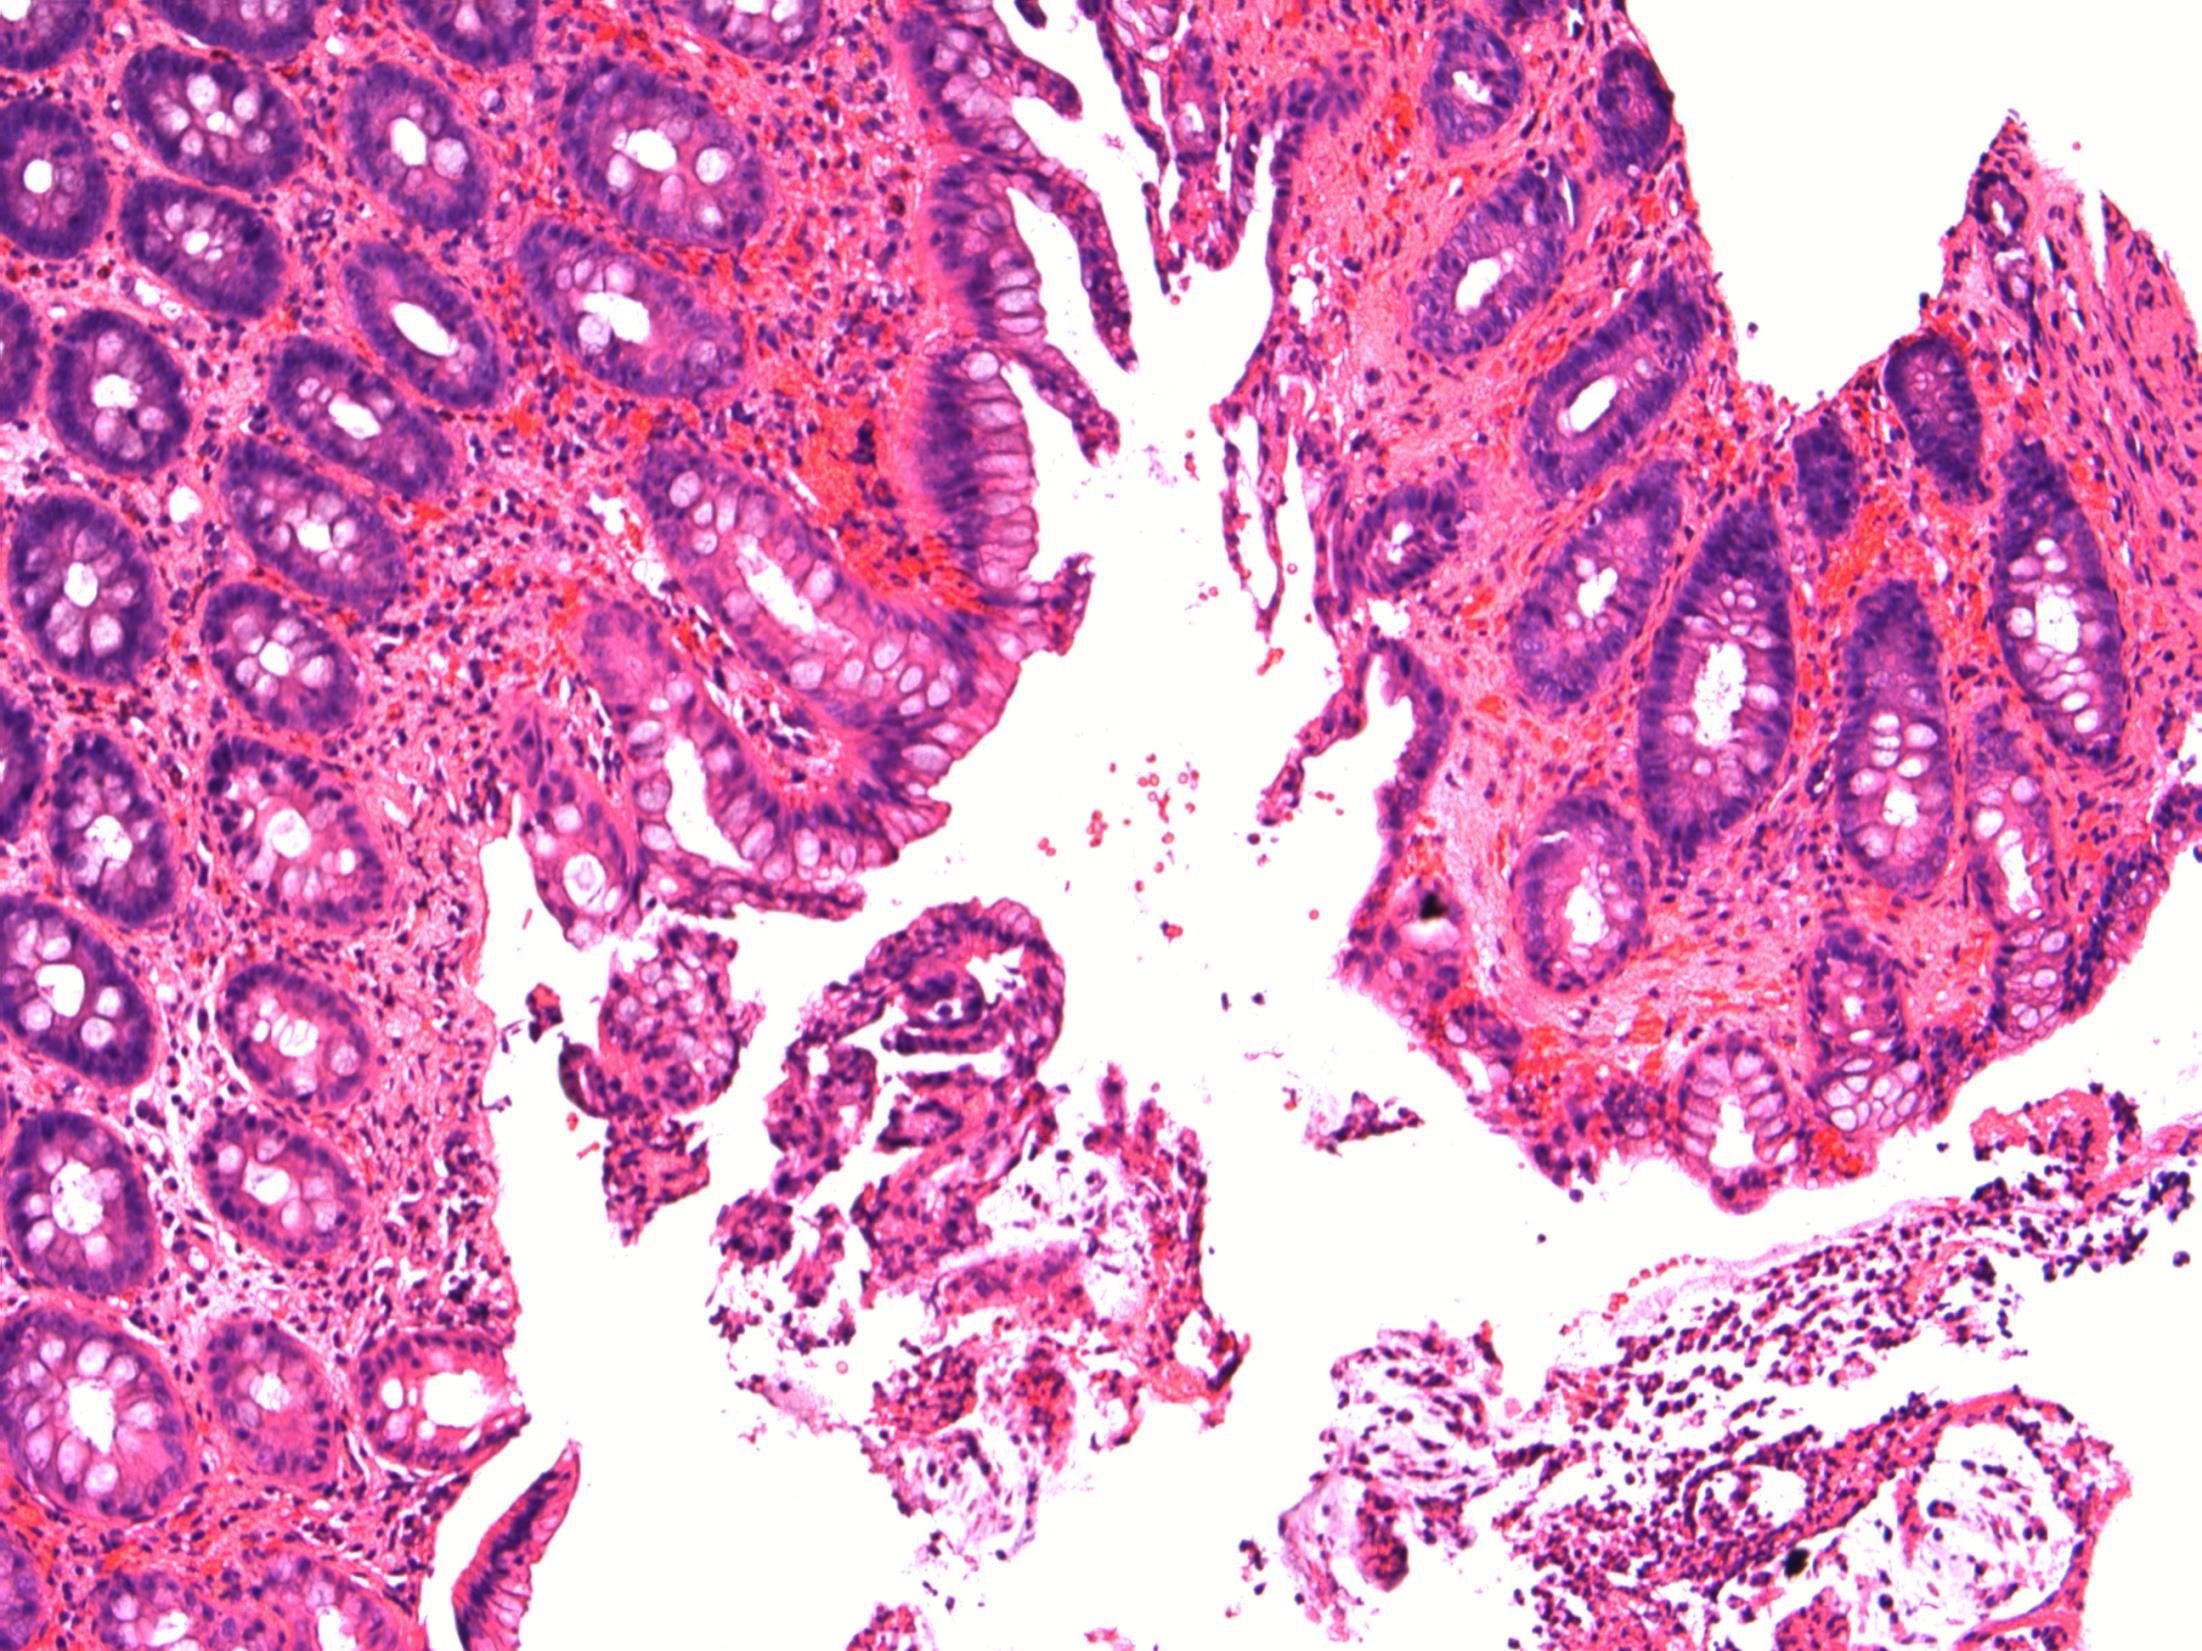

Giardiasis

Description: Small bowel mucosa of normal architecture. Trophozoites along the surface of epithelial cells. The organisms are teardrop/pear/comma shaped with paired nuclei. No evidence of malignancy. No evidence of coeliac disease.

Diagnosis: Giardiasis.

Plan: Correlate with clinical/travel history

Comments:

Protozoan infection associated with malabsorption and chronic diarrhoea (this lady had diarrhoea).

Spreads by faecally contaminated water, usually underdeveloped countries ( hence travel history important).